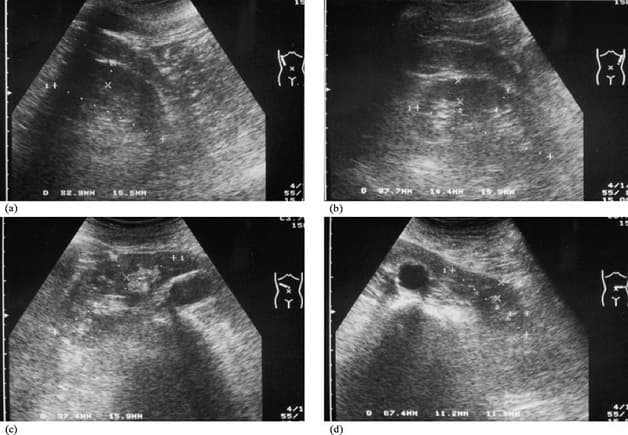

5.1. Siêu âm

Các hình ảnh thu được từ máy siêu âm sẽ cho thấy sỏi niệu quản đang ở giai đoạn nào. Phát hiện các dấu hiệu thận ứ nước, niệu quản giãn.

Siêu âm có thể giúp phát hiện sỏi